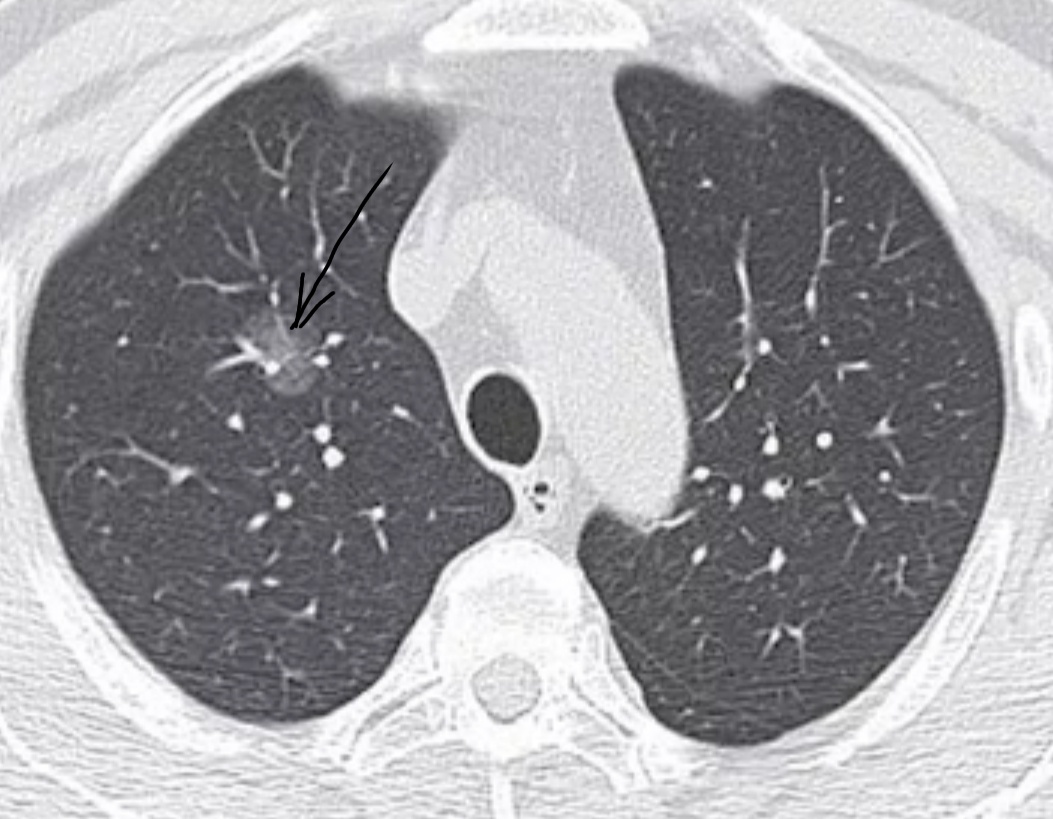

Во время прохождения диспансеризации в перечень обследований входит флюорография. К сожалению, часто она бывает малоинформативной, а лечить рак, выявленный с ее помощью, уже поздно. В снижении смертности от данного заболевания путем его раннего обнаружения. Рак лёгких является актуальной проблемой: он до сих пор остаётся одним из самых распространённых новообразований и входит в десятку причин смертности от онкологии. По мнению некоторых специалистов, к 2035 году смертность от рака лёгкого увеличится до 3 миллионов случаев в год. Это скрининговая процедура, во время которой доза Rg-излучения с помощью специальной программы составляет около 1 мЗв (для сравнения при флюорографии - около 0,5 мЗв, при цифровой - 0,3 мЗв). В данном случае протокол исследования немного изменен (уменьшена скорость вращения трубки), благодаря этому получаемая доза лучевой нагрузки снижена. Получается меньше аксиальных (поперечных) срезов, но информативность исследования не страдает. На флюорограмме рак на т

Преимущества низкодозной КТ перед обычной флюорографией